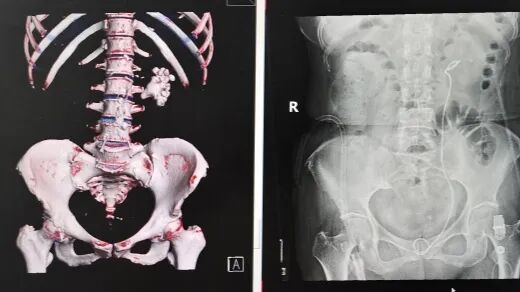

患者鄭奶奶因突發(fā)腰痛前往醫(yī)院就診,經(jīng)CT檢查結(jié)果顯示,其左腎已被結(jié)石完全填充,確診為典型的腎鑄型結(jié)石。腎鑄型結(jié)石因形態(tài)酷似鹿角,又被稱為鹿角形結(jié)石,這類結(jié)石會(huì)在腎臟內(nèi)長(zhǎng)期生長(zhǎng),逐漸填滿腎臟內(nèi)部空間形成整體形態(tài)結(jié)石,不僅治療處理難度極大,還伴隨極高的感染風(fēng)險(xiǎn)。